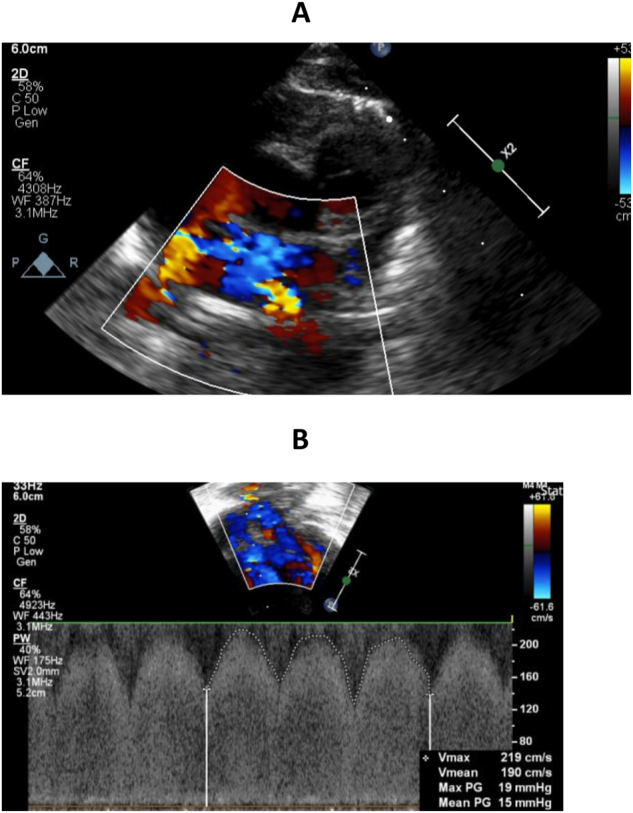

Case presentation: A preterm female infant born at 23+5 weeks gestation had numerous complications related to extreme prematurity, including BPD. She was diagnosed with PVS on echocardiogram after experiencing recurrent respiratory deteriorations and pulmonary hypertensive crises. Initial management involved transcutaneous balloon dilatation. A serial echocardiographic programme was implemented, with weekly monitoring of PVS. She suffered multiple respiratory deteriorations secondary to recurrence of PVS, necessitating repeat cardiac catheterisations and transcatheter stenting. Systemic macrolide therapy with sirolimus was used as adjunctive therapy.